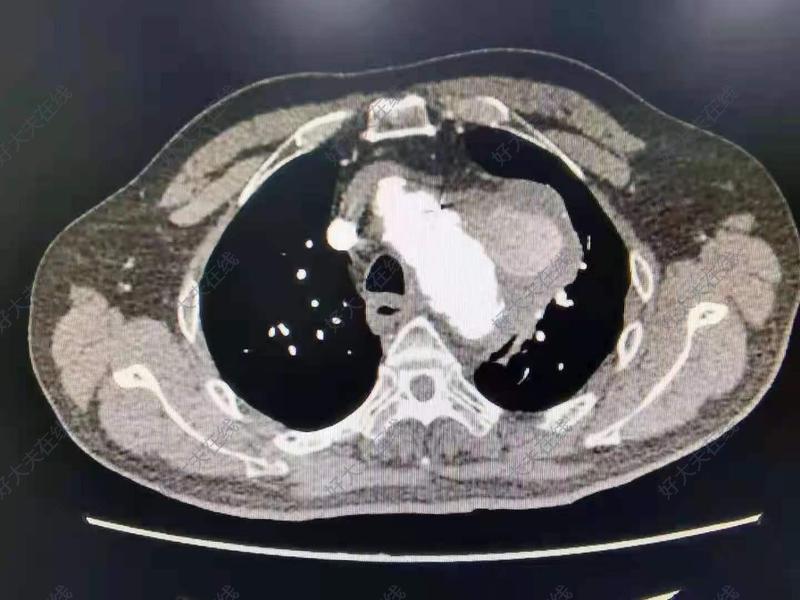

2022年7月21日,成功拆除人體炸彈一枚。患者,男,51歲。因反復(fù)咳嗽一月到醫(yī)院檢查發(fā)現(xiàn)主動(dòng)脈根部瘤,合并主動(dòng)脈瓣重度關(guān)閉不全。根部瘤直徑達(dá)76毫米,隨時(shí)有破裂,發(fā)生生命危險(xiǎn)可能。來(lái)我們醫(yī)院要求手術(shù)。今天在全麻體外循環(huán)下成功拆除人體炸彈,用27號(hào)帶瓣管道行主動(dòng)脈根部置換術(shù)。主動(dòng)脈瘤號(hào)稱“人體炸彈”,一旦破裂,病人會(huì)形成夾層或大出血危及生命。主動(dòng)脈瘤切除是我們科常見手術(shù),當(dāng)主動(dòng)脈直徑大于55毫米時(shí)必須手術(shù)治療,直徑越大破裂的危險(xiǎn)性越高!